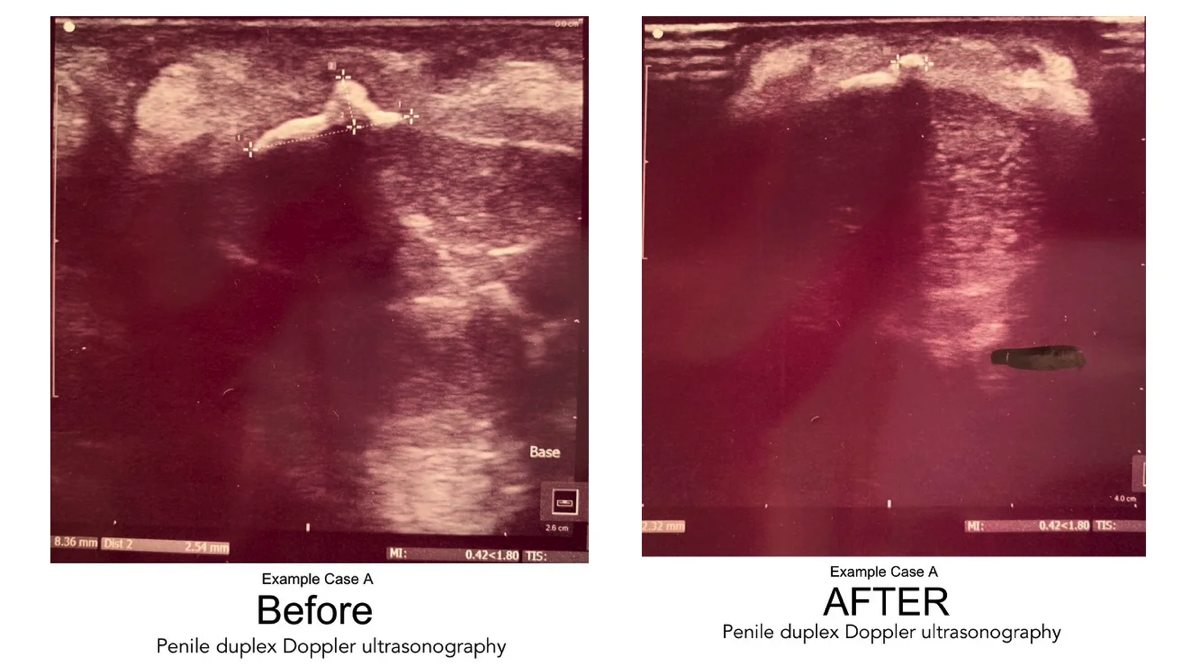

Highlights: Calcified Plaque Before & After Sonogram Images

Following is a set of four "before and after" duplex sonogram images of Peyronie's patients with calcified plaques